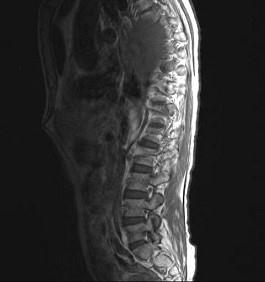

常见的椎管内肿瘤(如图所示)有()A.脊膜瘤B.胶质瘤C.血管瘤D.上皮样囊肿E.神经鞘瘤

问题 常见的椎管内肿瘤(如图所示)有()

选项 A.脊膜瘤 B.胶质瘤 C.血管瘤 D.上皮样囊肿 E.神经鞘瘤

答案 ABCDE